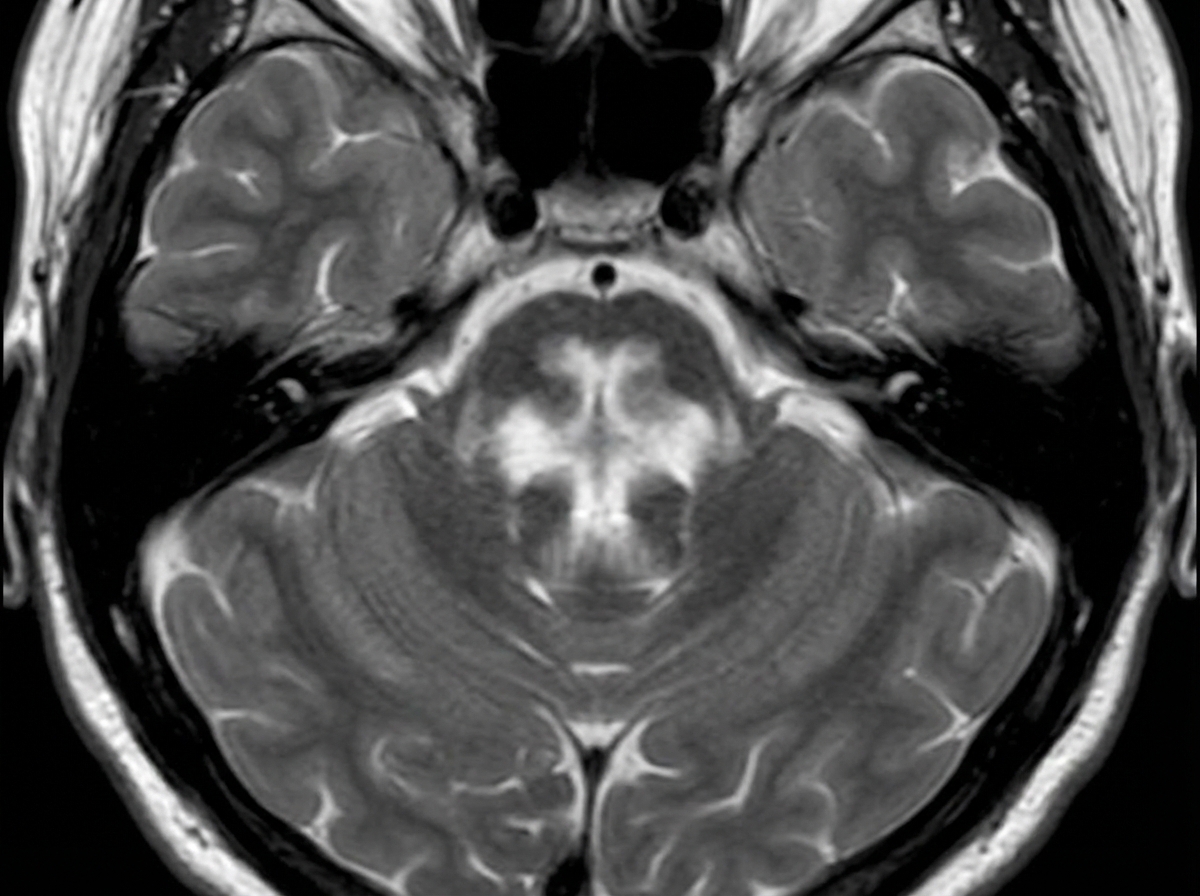

A 60-year-old male patient presented with spasticity in bilateral lower limbs. An MRI was performed and is shown below. What is the most likely diagnosis?

Explanation: ***Multiple system atrophy with predominant cerebellar ataxia*** - The **hot cross bun sign** on MRI is pathognomonic for **MSA-C**, showing cruciform hyperintensity in the pons due to selective neuronal loss. - Bilateral lower limb spasticity indicates **pyramidal tract involvement**, which is characteristic of MSA-C along with cerebellar dysfunction. *Multiple system atrophy with predominant parkinsonism* - **MSA-P** typically shows the **putaminal rim sign** on MRI (hyperintense rim around the putamen), not the hot cross bun sign. - Clinical presentation would focus on **parkinsonian features** (bradykinesia, rigidity) rather than predominant spasticity. *Progressive supranuclear palsy* - **PSP** demonstrates the **hummingbird sign** or **penguin sign** on sagittal MRI due to midbrain atrophy. - Clinical features include **supranuclear gaze palsy** and **axial rigidity**, not bilateral lower limb spasticity. *Lewy body dementia* - **MRI findings** in Lewy body dementia are typically **non-specific** with mild cortical atrophy. - Clinical presentation involves **cognitive fluctuations**, **visual hallucinations**, and **REM sleep behavior disorder**, not spasticity.